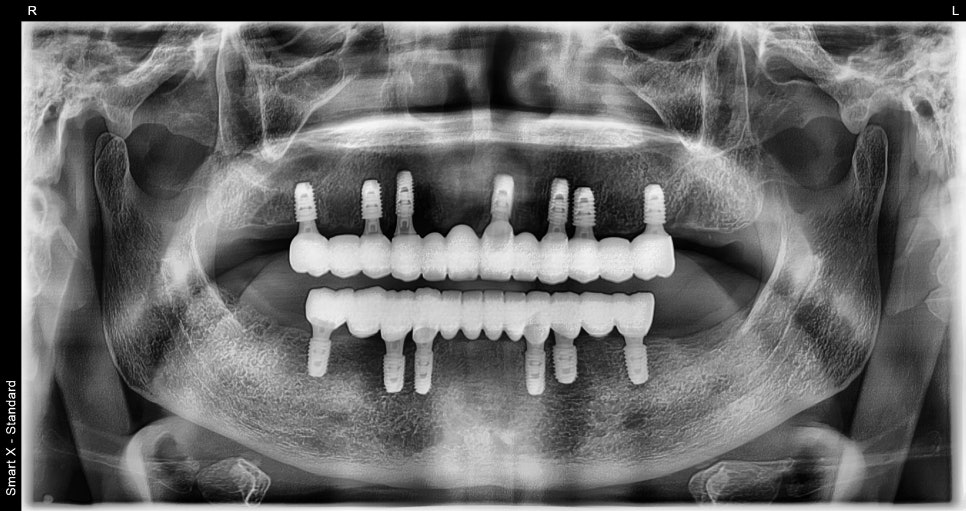

전체임플란트 최종 보철 완성

최종 보철 제작 시 다음 사항을 중심으로 설계했습니다.

잇몸 라인과 자연스럽게 맞닿는 형태

어금니 중심의 안정적인 교합

발음과 저작 기능 개선

기공 단계에서 미세 오차 반복 체크

장착 후 앞니와 어금니 모두 균형 있게 맞물리며

음식의 질감을 충분히 느낄 수 있는

교합으로 복원되었습니다.

서울오브치과병원 임플란트 후

<수술 후>

환자분의 삶의 질 변화는 매우 뚜렷했습니다.

정상적인 식사 가능

어금니 라인 복원으로 저작력 향상

발음 개선

표정 및 얼굴 윤곽 안정화

잇몸 염증 감소